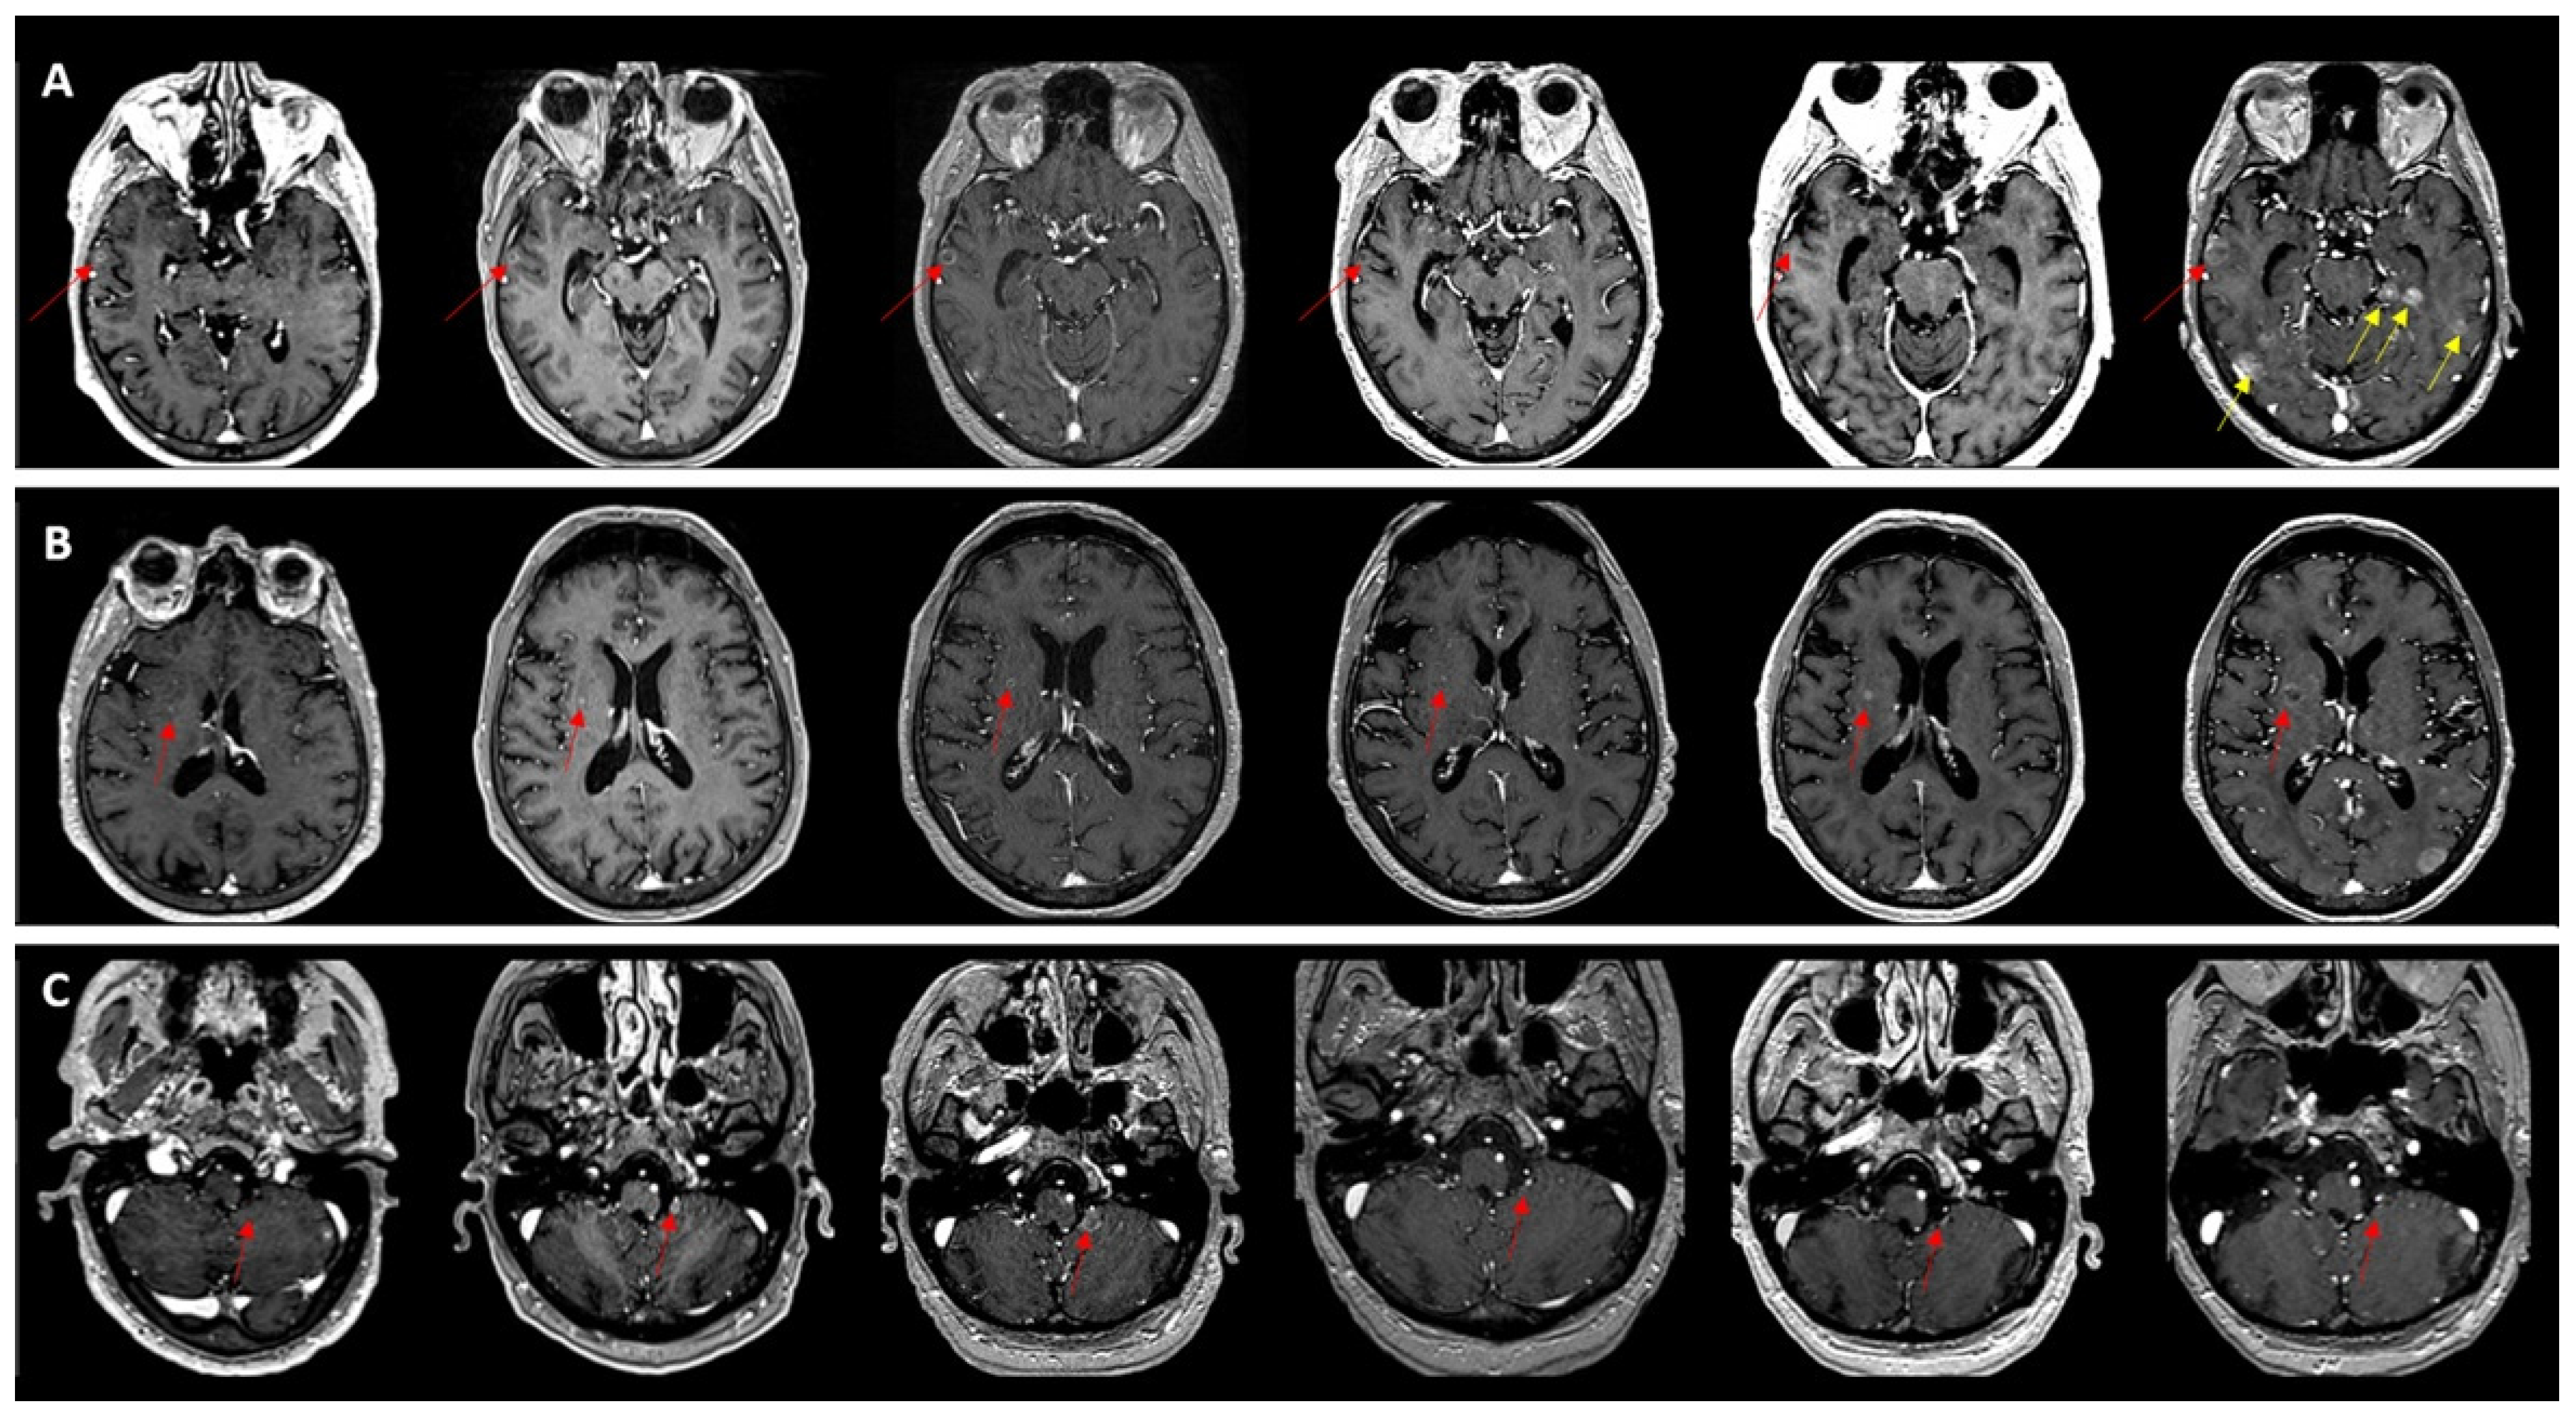

Figure 3. Evolution of a right cerebellar metastasis (red arrows) in a patient with breast cancer and multiple secondary lesions. (A) Before treatment MRI showed a 6 mm right cerebellar lesion with ring enhancement on post-contrast T1, no susceptibility artifacts on SWAN and hyperintense on T2/FLAIR. (B) At 8 weeks after whole-brain radiotherapy (30 Gy/10 fractions) with a sequential boost up to 45 Gy to the cerebellar lesion, there was dimensional regression with residual millimetric enhancement, the appearance of a hypointense susceptibility artifact on SWAN, and resolution of signal abnormalities on FLAIR. (C) At 6 months after radiotherapy, the lesion was no longer visible on conventional sequences; only a subtle punctiform hypointense focus on SWAN could be appreciated, which would not be recognized as a treated metastasis in the absence of longitudinal tracking.